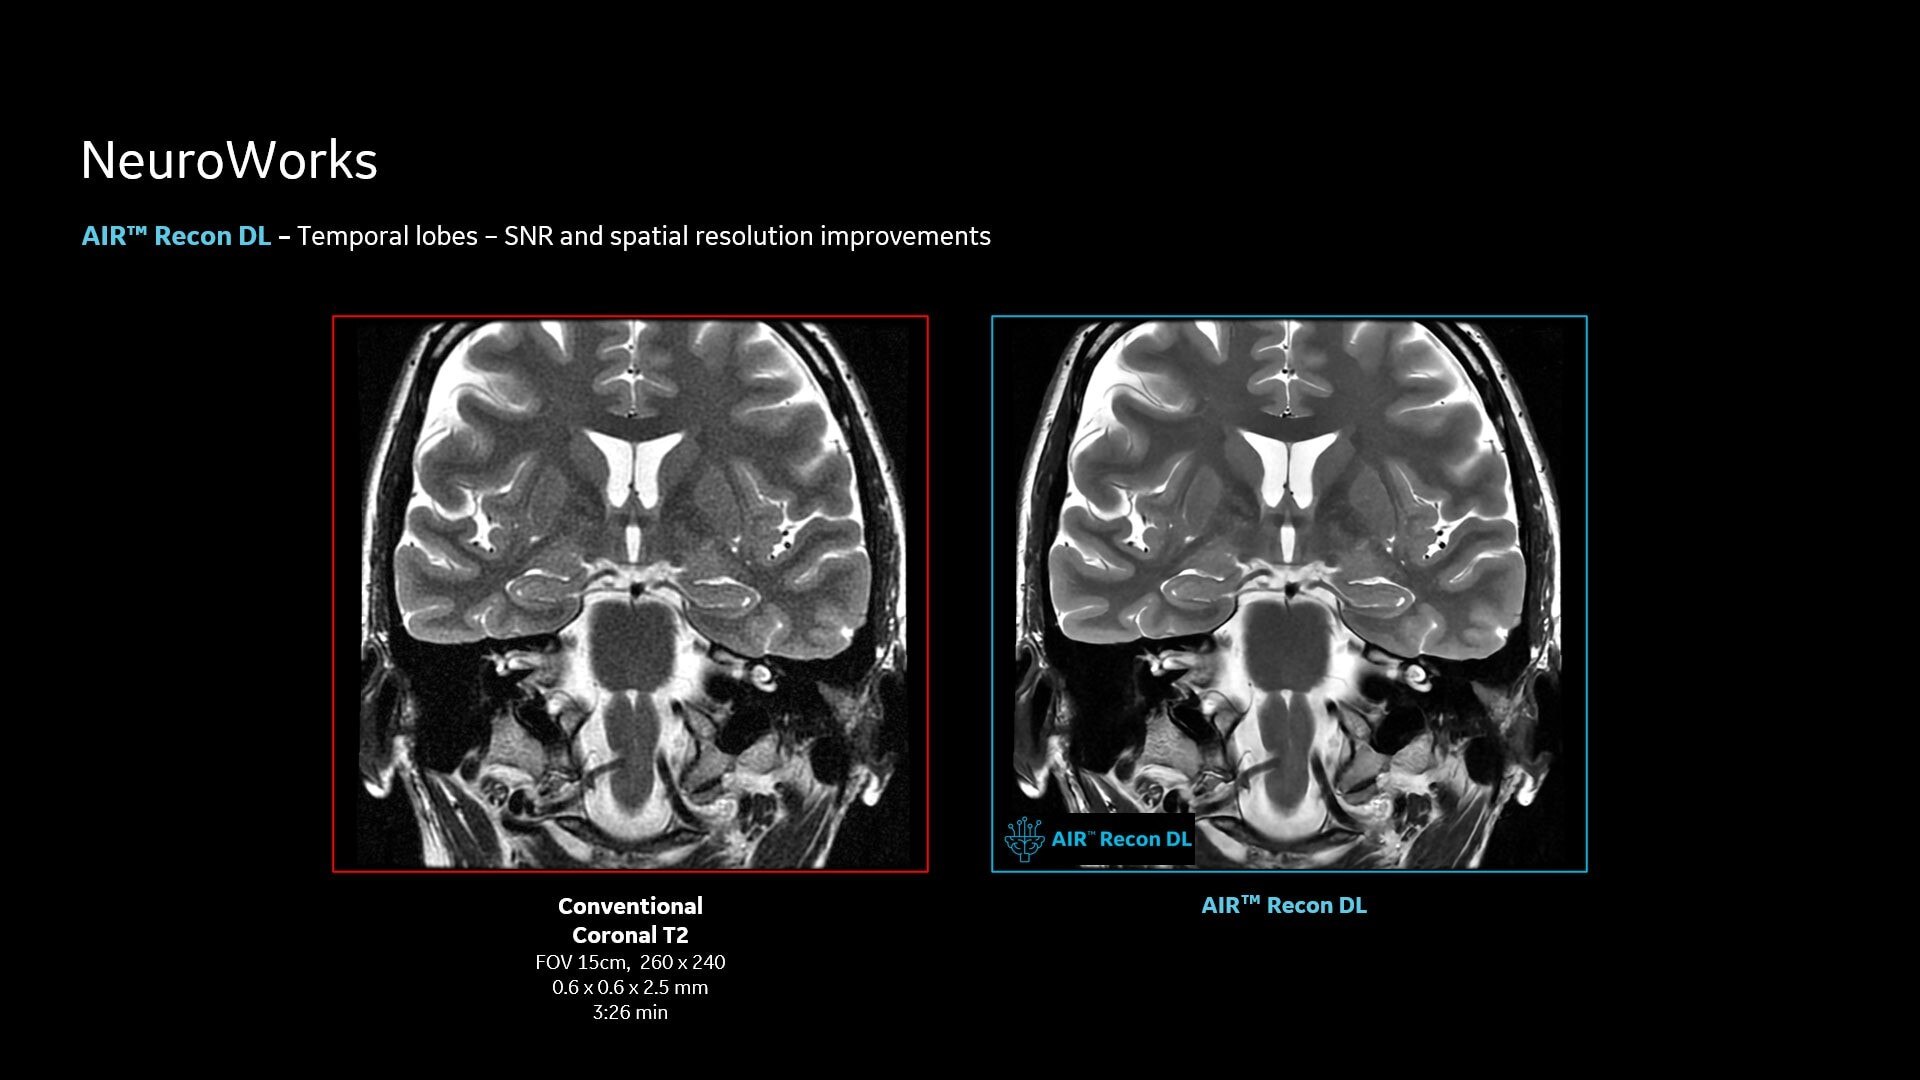

AIR™ Recon DL improves SNR and image sharpness, enabling shorter scan times

Up to 50% faster acquisition time with AIR™ Recon DL

Achieve a 25% efficiency gain with Ultra High Efficiency (UHE) gradient system. Fast, clear Total Digital Imaging (TDI) increases SNR by 25%. Improved IQ in 80% of cases without added time. Acquire higher SNR without a time penalty and get images virtually free of artifact with AIR™ Recon DL.***